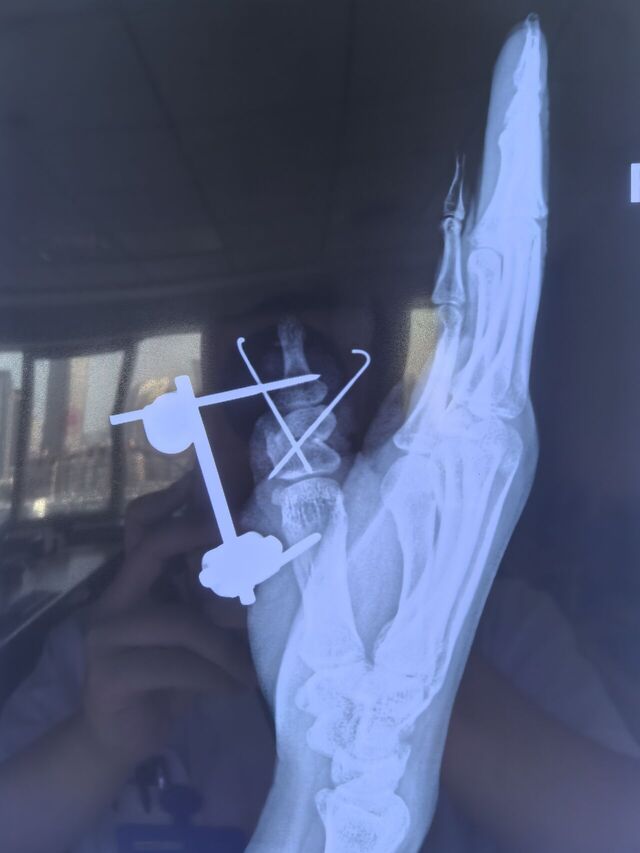

截骨矫形术

mmexport1754829508147.jpg